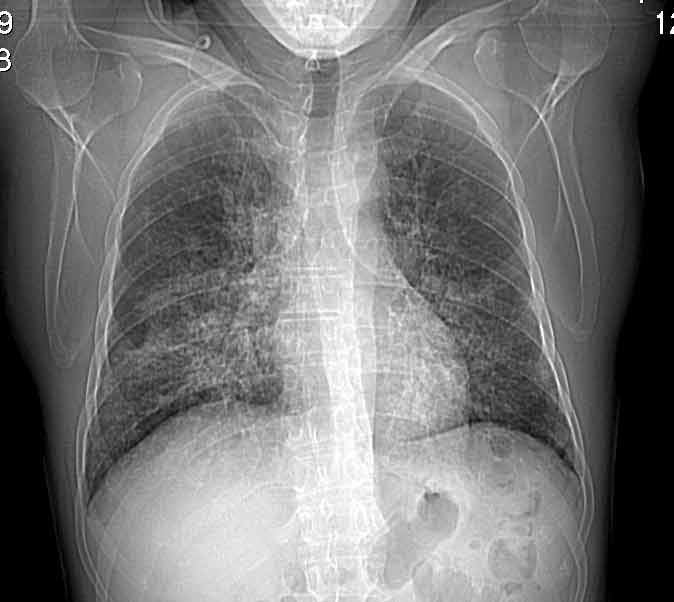

Случай №1

Женщина 50 лет.

Случай 1: изменения характерны для интерстициальной пневмонии (IIP/UIP idiopathic interstitial pneumonia/usual interstitial pneumonia); говорить о конкретной форме без открытой биопсии затруднительно.